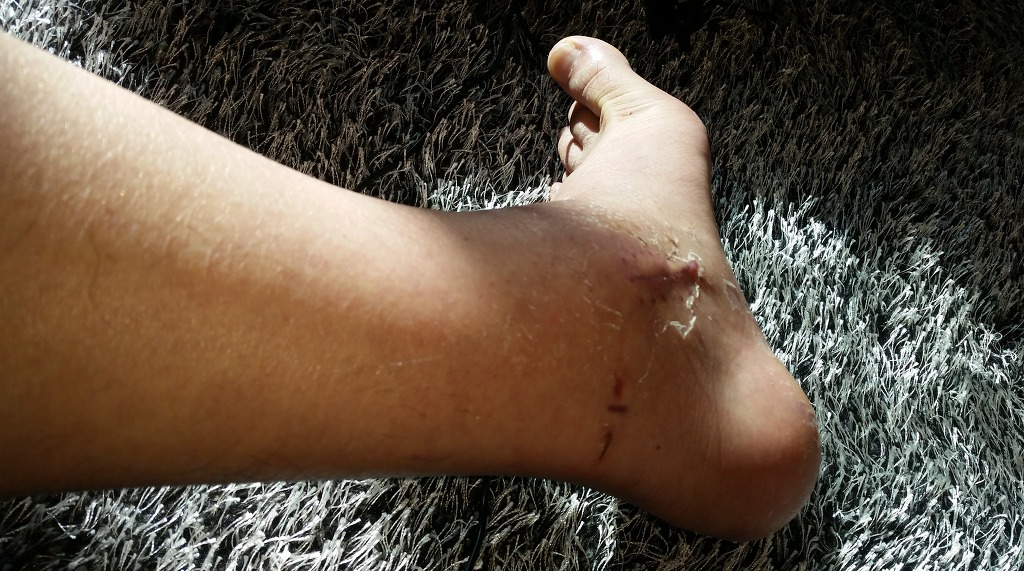

족욕을 자주하니 과거의 피부가 한꺼풀 벗겨지기 시작하고 새살이 생기네요. 보들보들한 느낌.

껍질이 한번 완전히 벗겨지고 새살이 나니 발이 많이 깔끔해졌네요 ㅎ ㅎ